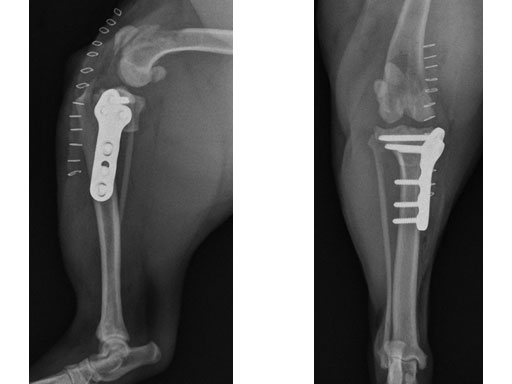

A four-year-old, female, spayed, 33 kg English bulldog had a CrCL tear and a medial patellar luxation. The small stature 3.5 mm TPLO plate was perfect for this dog due to the small profile of the bone and the need to use a heavier plate (3.5 vs a 2.7 mm). In the past, veterinary surgeons have been forced to either squeeze the standard TPLO 3.5 mm plate on the bone or use an undersized TPLO 2.7 mm plate. In this patient, the shorter and smaller profile head of the small stature TPLO 3.5 mm was perfect.